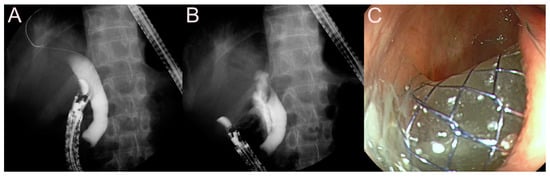

2.4. Stent for EUS-Guided Pancreatic Duct (PD) Drainage

2.4.1. Use of the Plastic Stent

2.4.2. Use of the SEMS